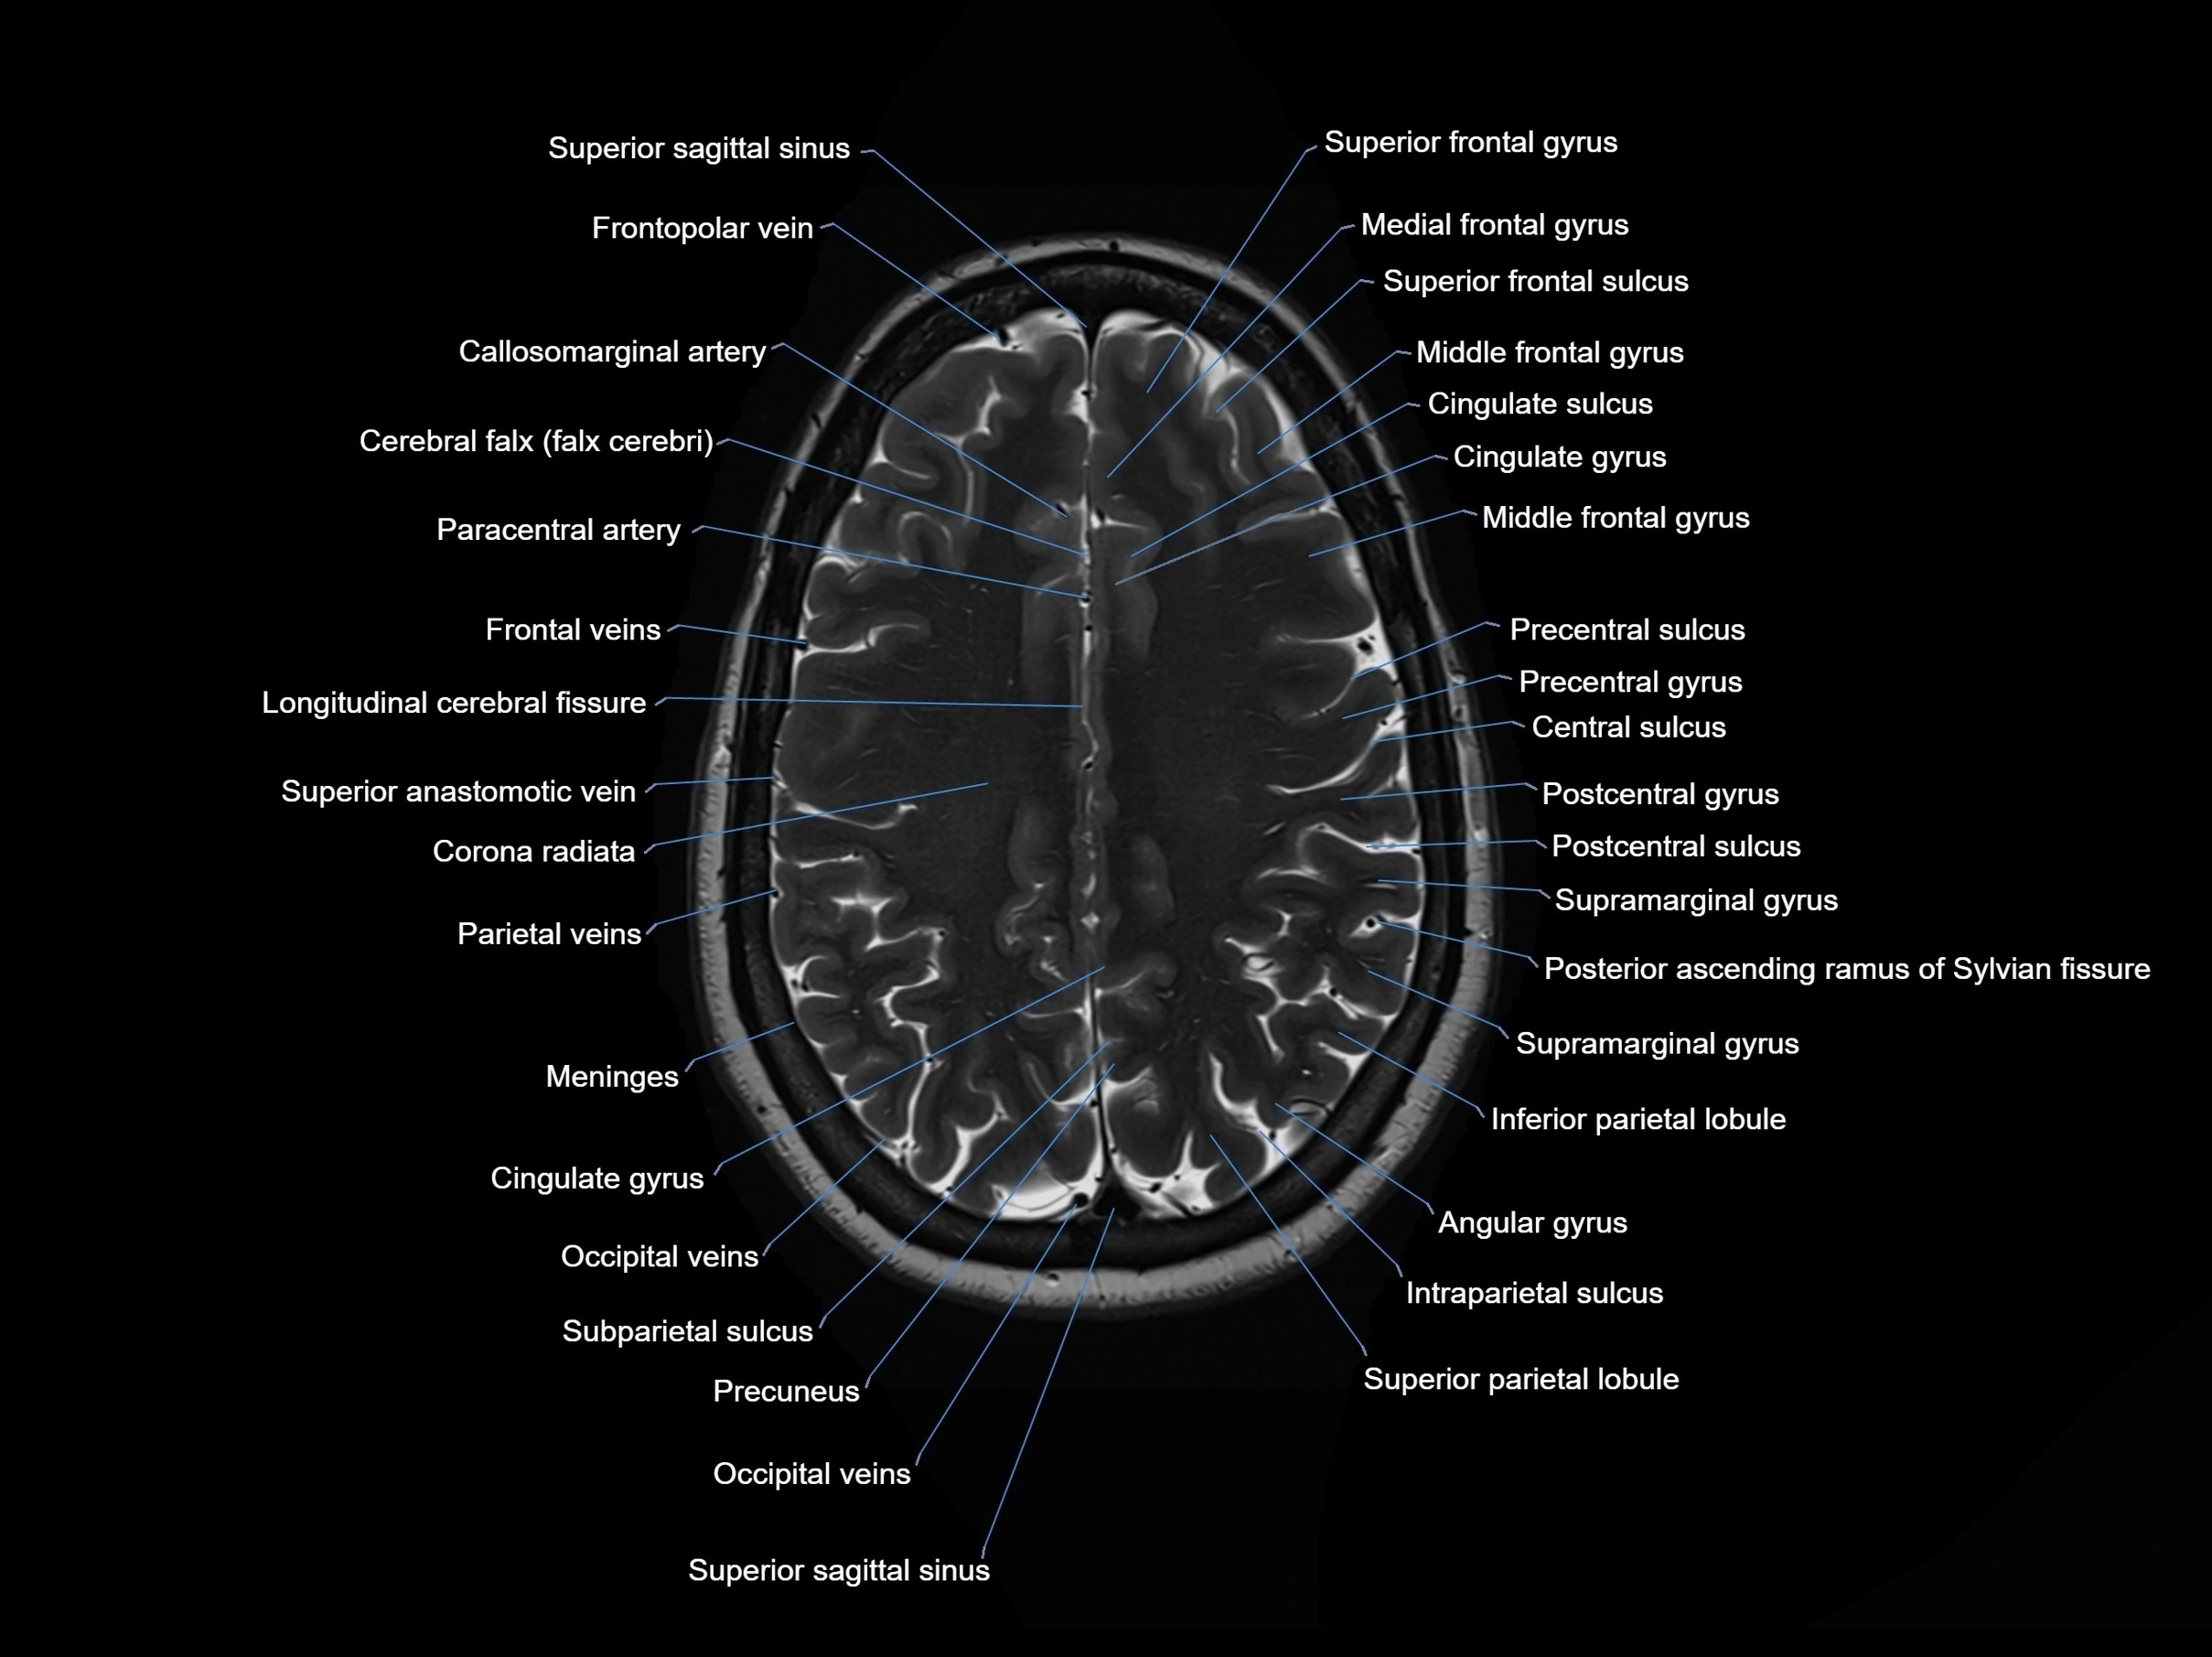

MRI images